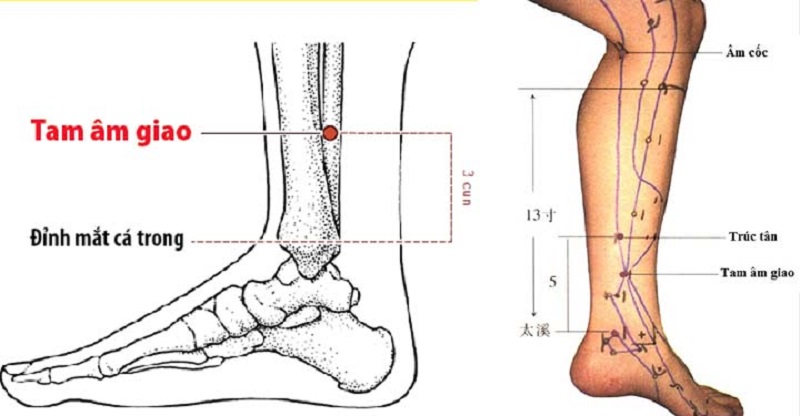

2. Huyệt tam âm giao

Vị trí: Bên trong cẳng chân, cách mắt cá chân khoảng 4 cm.

Cách bấm: Dùng ngón cái nhấn vào huyệt này trong 2-3 phút mỗi tối trước khi ngủ.

Tác dụng: Giảm căng thẳng, điều hòa khí huyết, cải thiện giấc ngủ.

- Bấm huyệt tam âm giao (cách mắt cá chân 4cm, phía trong cẳng chân) bằng ngón cái trong 1 phút.